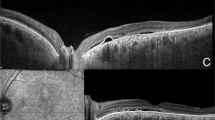

AN image that is physically fixed on the retina rapidly seems to fade1, and if the stabilization is good enough it never reappears2,3. We have some evidence that this process of fading is not entirely retinal, but is partly central, for we have noticed that an image free to move over the retina, but “stabilized” on the visual cortex, also becomes less distinct.